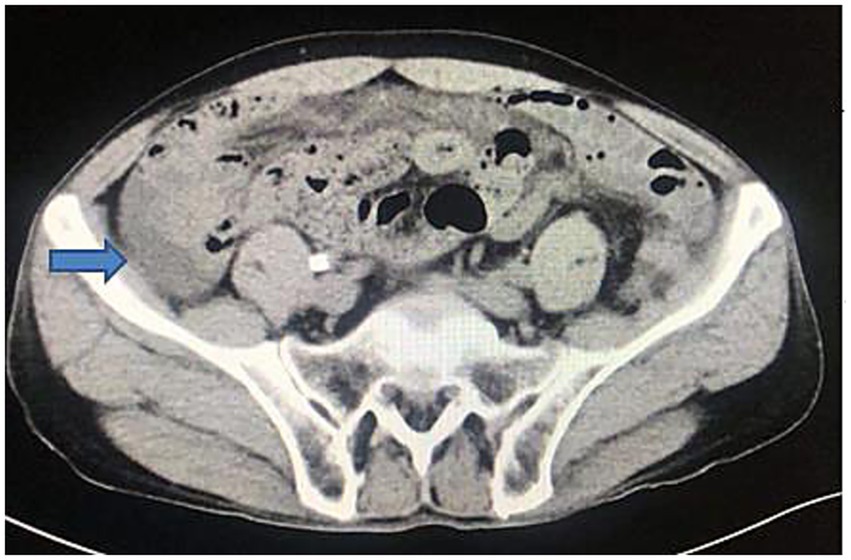

Abdominal computed tomography (CT) revealed mild intestinal dilatation within the abdominal cavity and abdominal fluid accumulation (Figure 1). Abdominal CT showed no tumor and cirrhosis. Abdominal color ultrasound showed no mesenteric vein embolism. A diagnostic abdominal paracentesis was performed, and opalescent ascites were visible (Figure 2). Subsequently, a percutaneous drainage procedure was conducted, resulting in the extraction of 400 mL of chylous fluid. Relevant laboratory tests examined the chylous fluid. The specific gravity of chylous fluid was 1.018, pH was alkaline (pH = 7.62), and protein content was 35 g/L. The cell count was low, with mostly lymphocytes (4.2 × 109/L) and a few neutrophils (0.8 × 109/L). The bacterial culture was negative. Droplets of fat could be seen under the microscope. Chylous fluid had high triglyceride content (3.85 g/L) and low cholesterol content (0.74 g/L), and cholesterol/triglyceride <1.0, leading to the diagnosis of chylous ascites. The patient did not present with any other significant illnesses at the time, prompting the implementation of conservative regimen measures such as water fasting, cefoperazone, somatostatin, and nutritional liquid containing glucose, fat emulsion, amino acids, vitamins, and trace elements. However, the abdominal pain was not relieved after 2 days, with about 600 mL of chylous ascites drained daily. Following the ineffectiveness of previous conservative regimen, laparoscopic exploration was considered the subsequent course of action.

Figure 1

Abdominal computed tomography showing abdominal fluid.